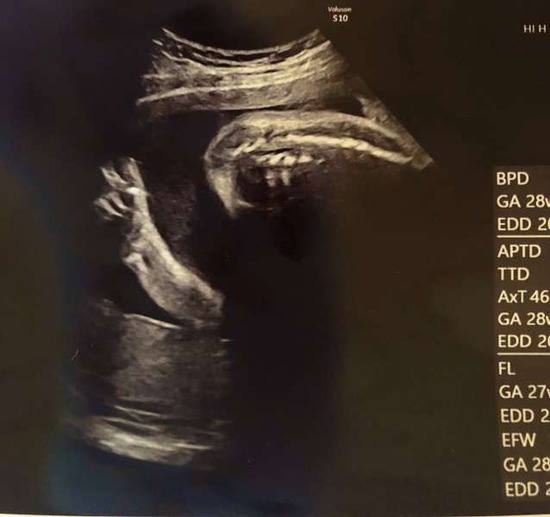

産まれる前の赤ちゃんがお腹の中からピース!?エコー検査の奇跡www

エコーで診ていた産科医も一緒にいた看護師さんも皆んな驚きの笑顔だったのだそう。